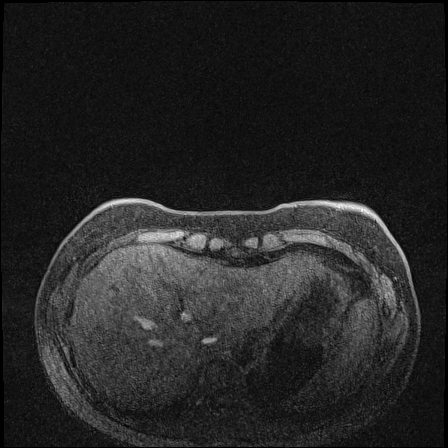

MRI images. The data used in this study are from the DUKE Breast Cancer Dataset [23], a comprehensive single-institutional retrospective collection of 3D MRI scans from over 900 patients with biopsy-confirmed invasive breast cancer at a university hospital. Each study includes a 3D MRI acquired using 1.5T or 3T scanners, from patients in the prone position. On average, each 3D scan consist of 250 2D slices (see Figure 1). For the predictive tasks, the slices are categorized into two groups: those containing breast tumors and those without. Following the approach of [15, 12], we establish a buffer zone between slices containing tumors and those that do not (highlighted in yellow in Figure 1(a)). Images within this buffer zone are excluded from analysis, and the remaining slices are labeled and used for the predictive task.

Magnetic field strength. 3T scanners offer higher magnetic field strength, improving signal-to-noise ratio (SNR) and image resolution for sharper, more detailed images [24]. However, they are more prone to artifacts, heating effects, and signal loss, especially around metal implants [5]. As such, our proposed dataset involving this spurious signal features a non-local spurious signal that influences the entire image rather than a localized region. An example set of images obtained from 1.5T and 3T devices are provided in Figure 3, showing that it is visually not possible to distinguish 1.5T MRIs from the 3T ones.

Vertical orientation. Different from magnetic field strength, which affects the entire image globally, vertical orientation is a local feature that only alters the spatial arrangement of structures within the image. This transformation does not modify the underlying tissue characteristics or signal properties but instead introduces artificial correlations that models may exploit as shortcuts.